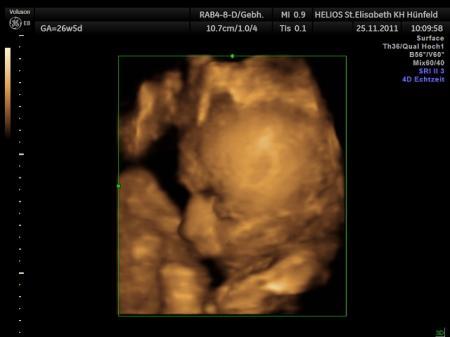

hallöchen ich bin heute in den 8 . monat gekugelt und war gestern beim großen ultraschall die kleine wiegt 1261 gr. und ist schon 37 cm groß . lg sabine

Bild zu